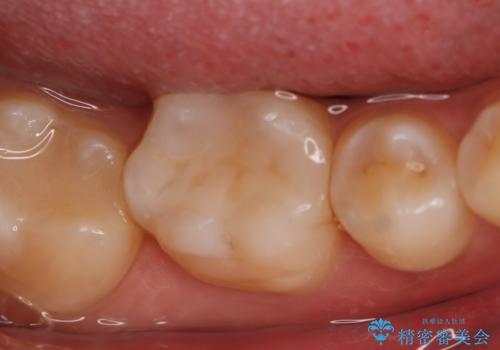

銀歯を白くしたい フルジルコニアクラウンとセラミックインレー

- 右上下6番の銀歯のやり変えを希望された患者様です。

切削量・形態を考慮し、上はセラミッククラウン、下はセラミックインレーでの治療を選択しました。

- 176000円(フルジルコニアクラウン、仮歯、セラミックインレー)費用は治療当時の料金となります